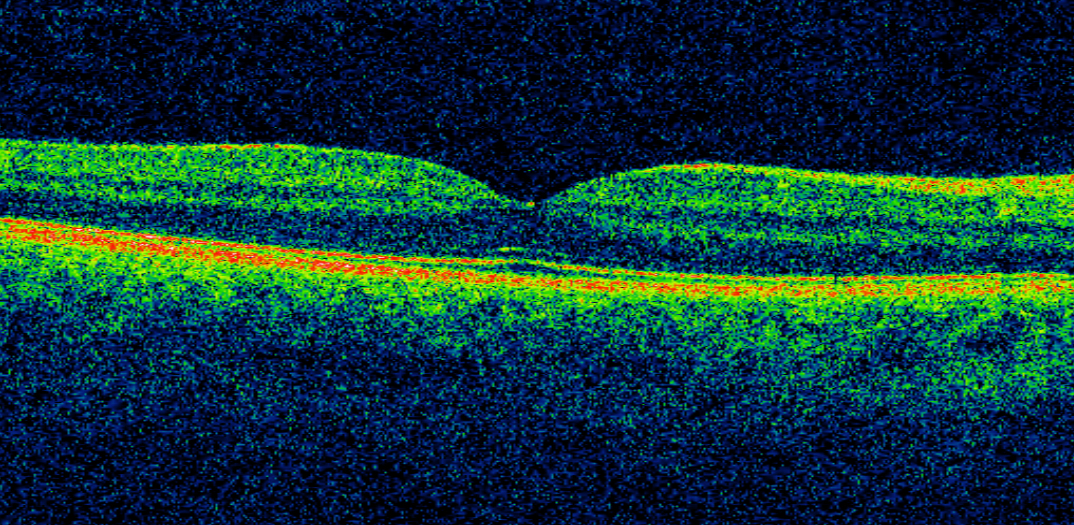

La IA de Google que venció al Go por fin hace algo útil al analizar dolencias oculares